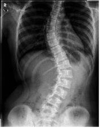

• 척추측만증, 10대에 막아라